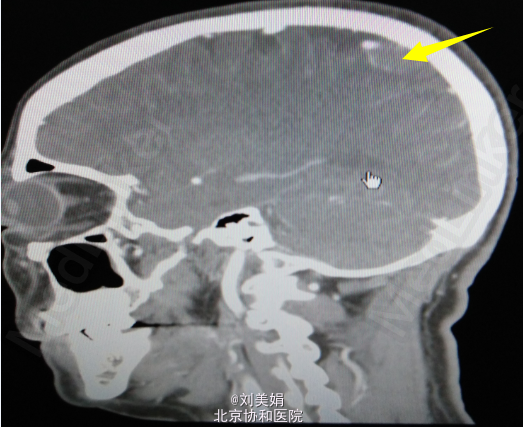

头增强CT:平扫图象显示:左侧顶部见一圆形略高密度影,边缘光整,边界清晰,大小约28.2mm×23.7mm,CT 值 68.2Hu,其内未见钙化,周围脑回受压、塌陷,脑室系统无扩大,脑沟裂未见增宽。中线结构未见明显移位。 增强图象显示:病灶明显均匀强化。CT 值为 92Hu,密度均匀,边缘清晰。右侧筛窦密度增高。

左顶部颅内占位性病变 神经导航下开颅窦旁脑膜瘤切除术